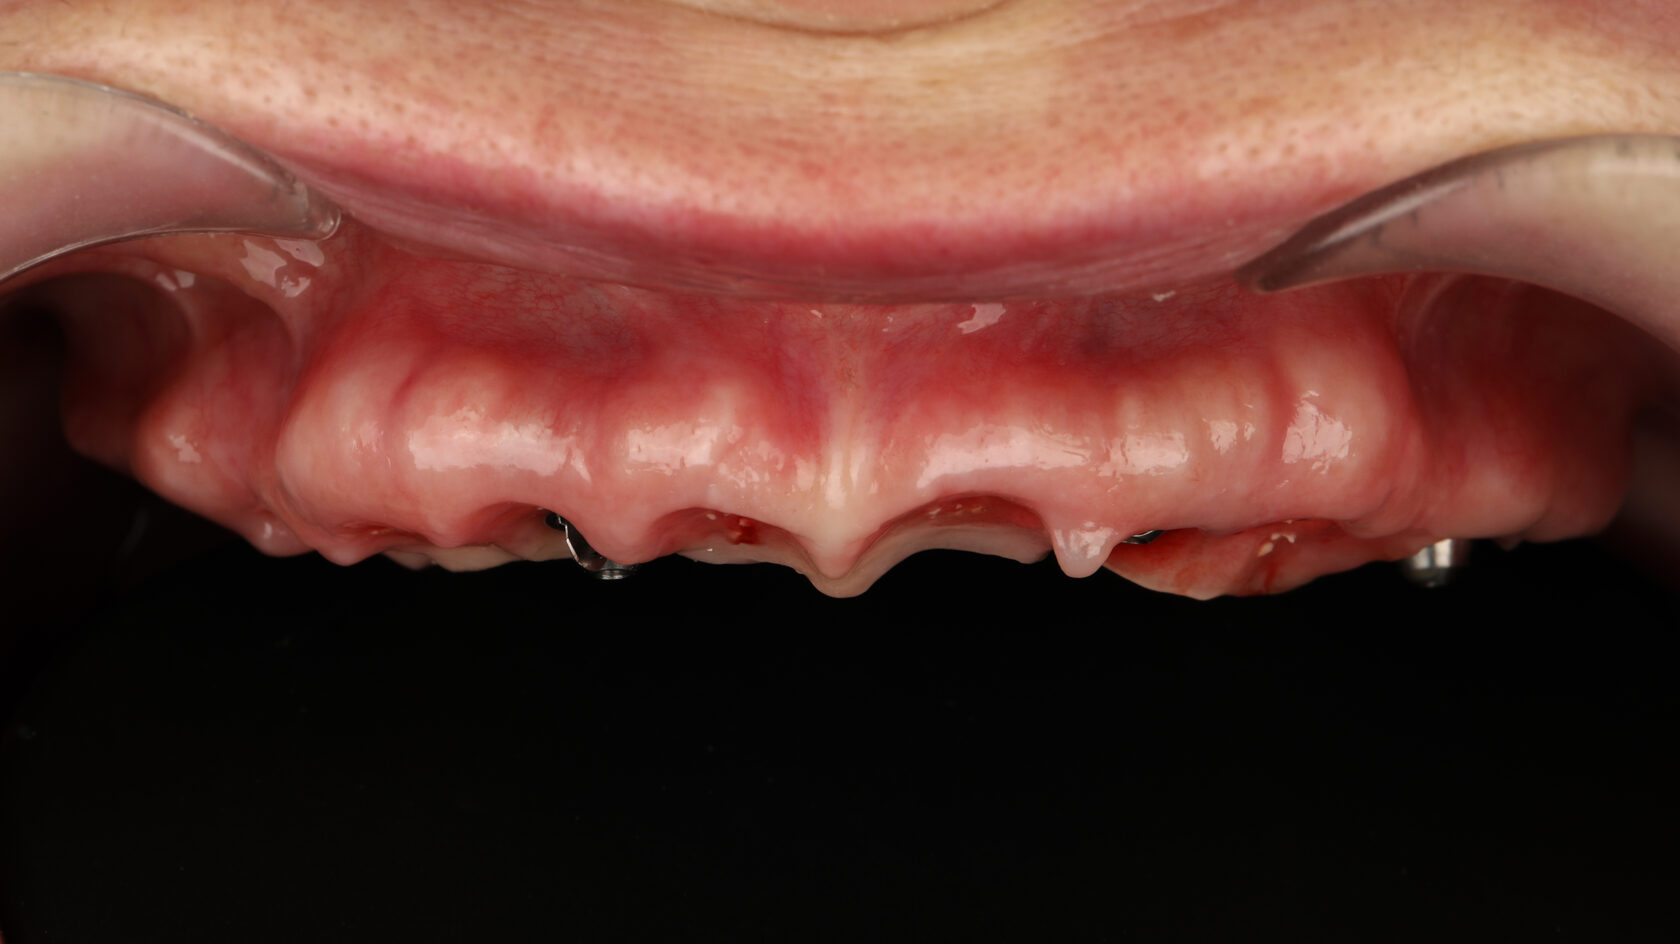

Цифровые протоколы немедленной нагрузки с экстремальной степенью атрофии

От 4 до 6 имплантатов (Maxila on4/ on 5/ on 6) Длинные имплантаты (небный и транссинусальный подход) Скуловые, птеригоидные, назальные имплантаты (транссинусальная, трансназальная постановка)

Разбор Free hands протоколов- итальянская техника от JDental Care! Насо - палатинальная постановка Трансинусальная постановка с фрезами JDNasal Трансназальная постановка с фрезами JDNasal по протоколу Nasa consept Протокол установки скуловых имплантатов anterior/posterior zygomatic по протоколу Zaga concept Трансинусальная и стандартная постановка птеригоидного имплантата Paga Concept